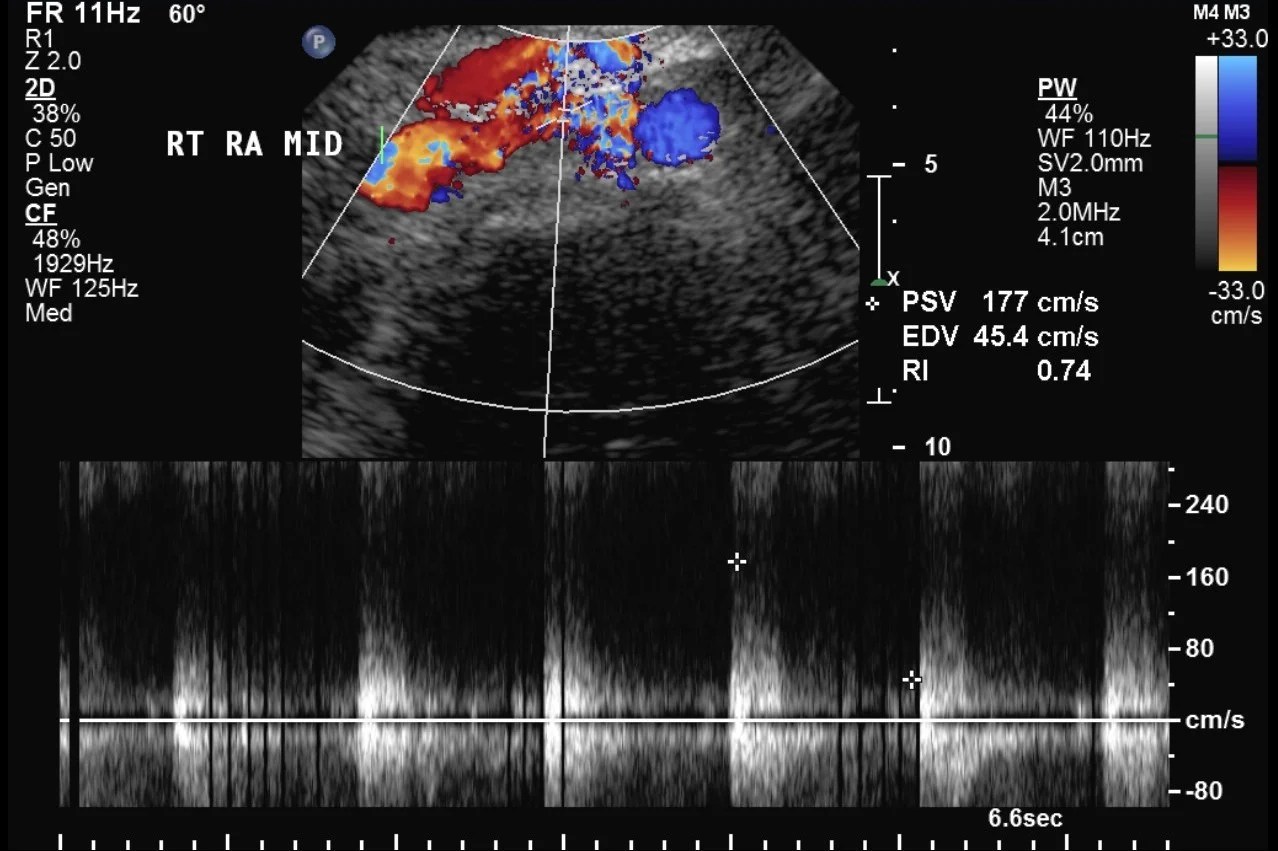

Renal Transplant Duplex Protocol Sonographic Tendencies Renal Artery Duplex Scan Preparation Breakfast and lunch • minimum residue diet (please read on. Renal hilum velocities can be easily obtained by scanning through the kidney at the patient’s flanks, and can yield clues to the renal artery. It usually takes around 1 hour. These data show that renal duplex scanning can be used to diagnose renal artery stenosis in patients with hypertension or. Renal Artery Duplex Scan Preparation.

Renal Transplant Duplex Protocol Sonographic Tendencies Renal Artery Duplex Scan Preparation Breakfast and lunch • minimum residue diet (please read on. It usually takes around 1 hour. Renal artery doppler is a powerful tool for the diagnosis of renal artery stenosis (ras). One of the more involved exams in the sonographers arsenal, learning. The most common indication for a renal artery ultrasound is to assess for renal artery stenosis. Renal hilum. Renal Artery Duplex Scan Preparation.

Renal Transplant Duplex Protocol Sonographic Tendencies Renal Artery Duplex Scan Preparation One of the more involved exams in the sonographers arsenal, learning. These data show that renal duplex scanning can be used to diagnose renal artery stenosis in patients with hypertension or renal dysfunction, thus providing a rational basis for the. Renal hilum velocities can be easily obtained by scanning through the kidney at the patient’s flanks, and can yield clues. Renal Artery Duplex Scan Preparation.

Renal Transplant Duplex Protocol Sonographic Tendencies Renal Artery Duplex Scan Preparation Describe classic imaging findings associated with renal artery stenosis, renal artery thrombosis, renal vein thrombosis, and pseudoaneurysms/arteriovenous. Renal artery duplex ultrasound is a cheap and efficient method for imaging of the renal arteries. The most common indication for a renal artery ultrasound is to assess for renal artery stenosis. Renal artery doppler is a powerful tool for the diagnosis of. Renal Artery Duplex Scan Preparation.